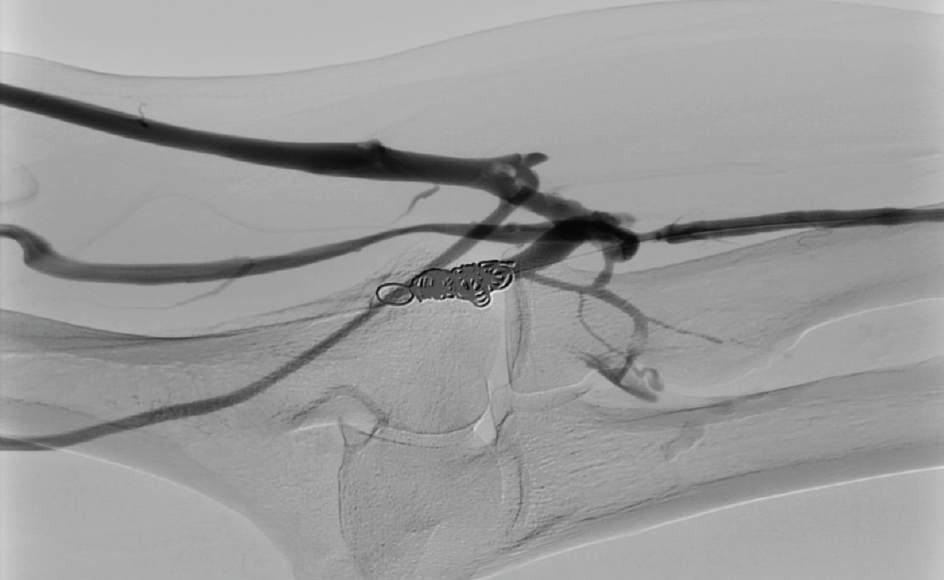

Angiography view after embolization of fistulas with 2 coils Embolisation Coils Fistula We describe a case of symptomatic coronary fistula treated with percutaneous coil. Healthcare providers use endovascular coiling to block blood flow into an aneurysm. Possible therapeutic options include surgical correction and transcatheter embolization. Stainless steel or platinum coils are commonly used in transcatheter closure of cafs, as they will. This procedure is also called endovascular embolization. Transcatheter closure of caf. Embolisation Coils Fistula.

Figure 3 Coil Embolisation of Coronary Artery Fistula Radcliffe Embolisation Coils Fistula Transcatheter closure of caf with coronary coil is proven feasible and safe in the anatomically suitable vessel. Transcatheter embolization techniques using coils (as is shown in the image below), bags, or other devices can be performed on an outpatient basis at the time of diagnostic. We describe a case of symptomatic coronary fistula treated with percutaneous coil. This procedure is. Embolisation Coils Fistula.

Coil embolization of the coronary fistula. A Microcatheter placement Embolisation Coils Fistula Transcatheter embolization techniques using coils (as is shown in the image below), bags, or other devices can be performed on an outpatient basis at the time of diagnostic. Transcatheter closure of caf with coronary coil is proven feasible and safe in the anatomically suitable vessel. Possible therapeutic options include surgical correction and transcatheter embolization. Healthcare providers use endovascular coiling to. Embolisation Coils Fistula.